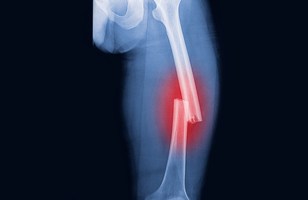

A fracture is a condition of breaking and cracking bones. The bone may fracture several types crosswise, lengthwise, into several pieces from several places. It is due to a change in the structure or shape of a bone. Certain medical conditions may also lead to the fracture of the bone. Medical conditions that weaken the bones include cancer or osteoporosis.

The severity of a fracture is commonly determined by the impact that caused it to break. The intensity of an external force acting on the bone makes them bend or break. If the breaking point of the bone is surpassed, the bone may snap rather than break exhaustively. On the other hand, the bone may shatter if the force is too strong, like in an accident or a bullet. There are different kinds of fractures. The features of a bone fracture can typically help healthcare professionals to categorize it majorly as follows: